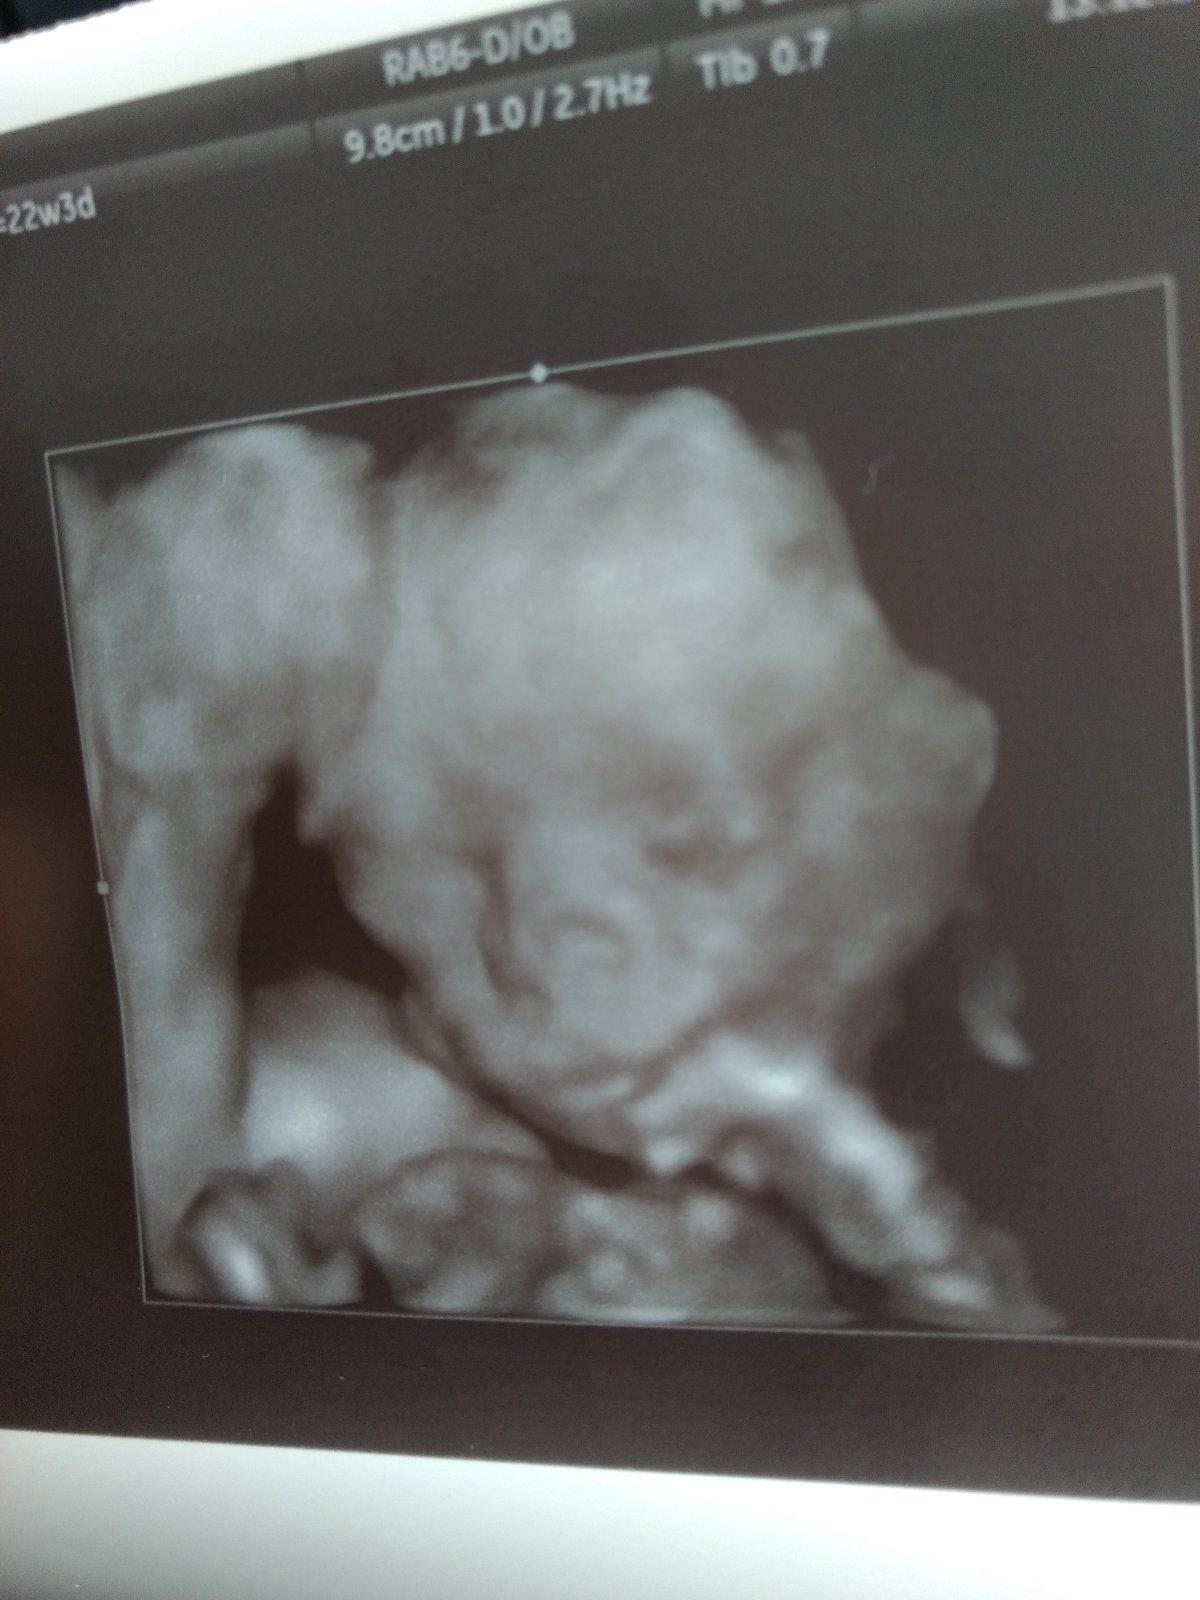

@karmela ďakujem moja 💙 áno asi tak nejako lebo dr len pozrel a hovorí ale veľký pipík má 😂🙈 som odpadla v ten moment. Potvrdený chlapec od dvoch doktorov 💛 takže ten už neodpadne 😝. Juuj teším sa že má také pery ako ja fešák po mamke 😍 ocko je nadšený takže budeme mať malého Radka po ockovi 💚

@karmela a ja som tak veľmi chcela dievčatko ❤️ no nevadí ja sa teším aj na krtka strašne ho milujem a keď vidím na sone čo si tam vystrája a tieto fotky na chladničke nalepené to je láska na prvý pohľad takže nie som ani sklamaná ale som vďačná Bohu že nám ho poslal po dlhej a náročnej ceste. A keď to pôjde a bude sa dať tak budem bojovat aj o druhé tehotenstvo ako o to prvé určite chcem dve detičky to už viem teraz. Takže rozumiem tomu mojko 😘 len nech sú zdravé tie naše detičky ❤️